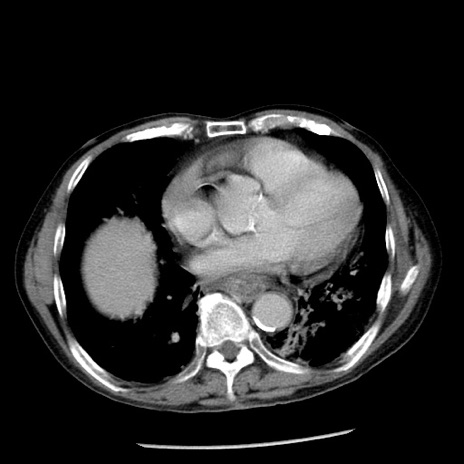

症例26(横断像)

【症例】80歳代男性

【主訴】嘔吐

【現病歴】昨晩2回嘔吐あり、今朝になっても嘔吐あり。来院。

【既往歴】胃潰瘍

【身体所見】意識清明、BT 37.6℃、BP 166/95mmHg、HR 100bpm、SpO2 97%、腹部:平坦・軟、腸蠕動音聴取良好、圧痛なし。

【データ】WBC 21900、CRP 1.46